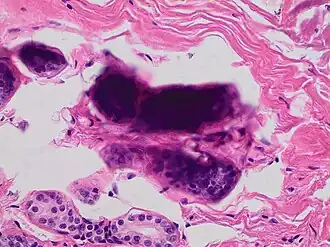

Pap stained smear of a monocyte with nuclear smearing or smudging artifact, seen as a tail-like extension of nuclear material -

Small cell carcinoma is a cancer where the presence of smudging is a clue to the diagnosis.[6]